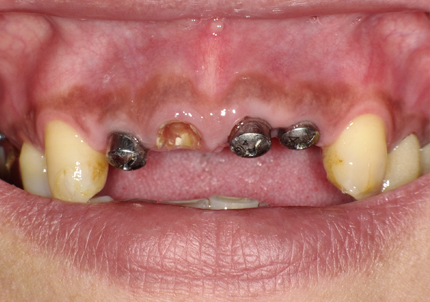

19.アバットメント装着(2020年1月)

ISQ値 右上2 (71) 左上1 (73) 左上2 (72)

20.最終補綴作製開始(2020年6月)